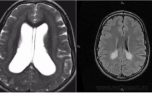

При визуальном осмотре лечащий врач не сможет диагностровать увеличение левого или правого желудочка мозга. Чаще всего после консультации невропатолога и выявления нарушенной координации, повышенного или пониженного тонуса мышц больной направляется на УЗИ.

Диагностика нарушения оттока и продуцирования ликвора проводится с помощью следующих инструментальных методов: компьютерная томография, магниторезонансная томография, нейросонограмма, офтальмологическое обследование глазного дна, пункция ликвора.